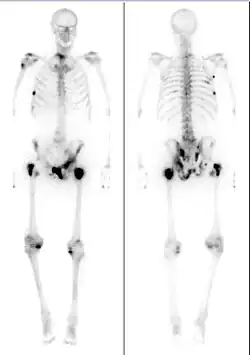

Medical image showing a man's skeleton with several dark spots along the bones

Bone scintigraphy scan of a man with metastatic prostate cancer. Dark spots indicate metastases along the pelvis, ribs, and shoulder.